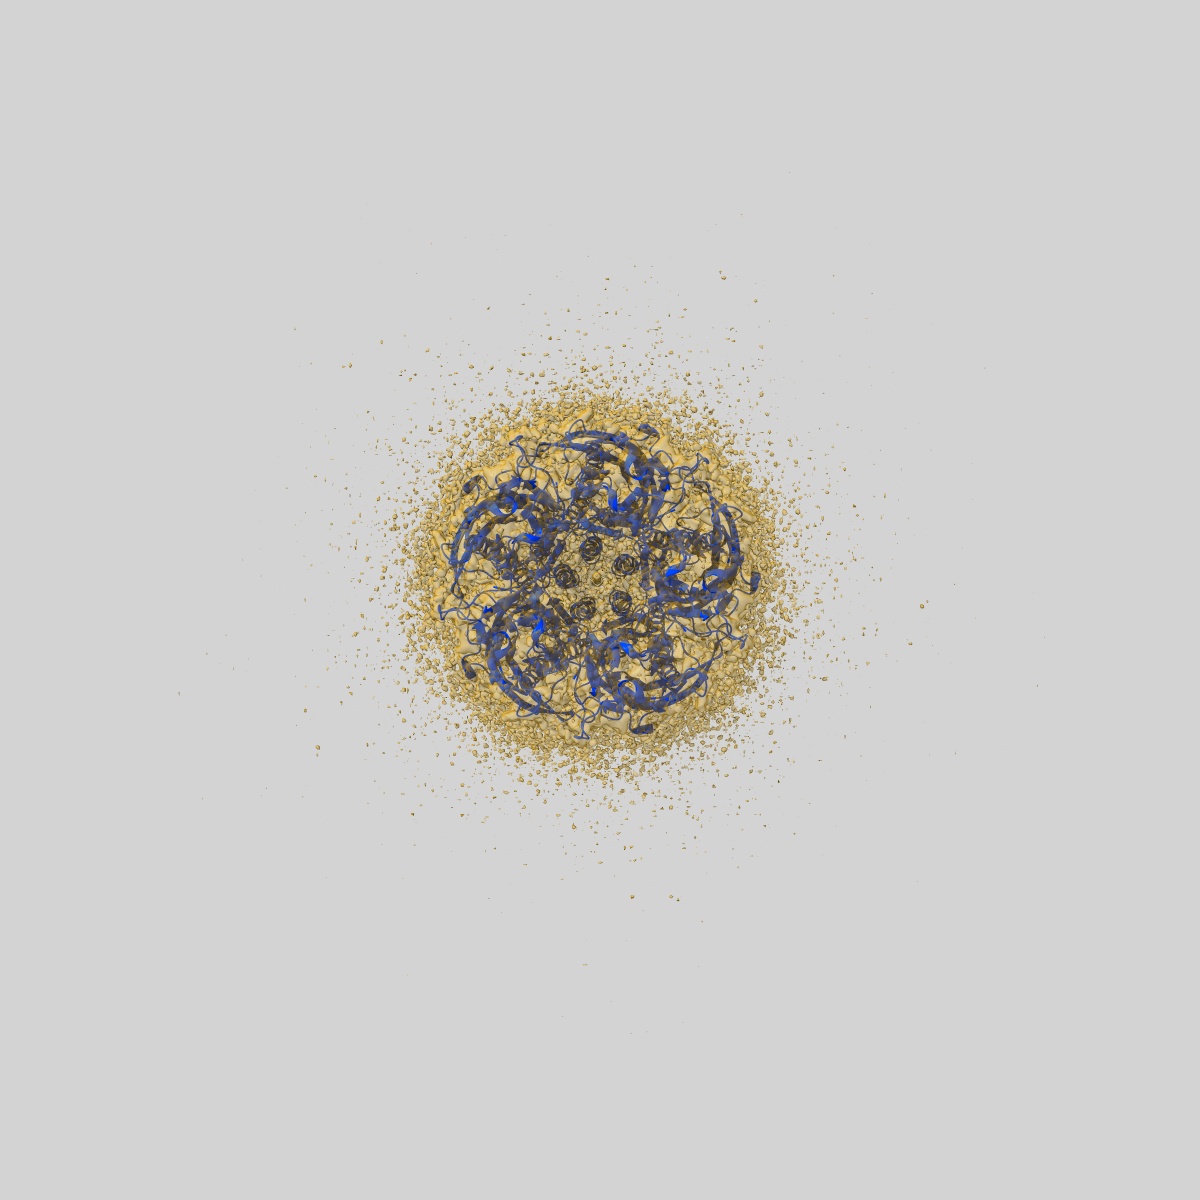

CryoEM structure of human rho1 GABAA receptor in complex with (R)-GABOB in the primed state

Sample: human rho1 GABAA receptor

Fitted models: 9frh

Cryo-EM structures of rho 1 GABA A receptors with antagonist and agonist drugs.

Fan C , Cowgill J , Howard RJ , Lindahl E

(2025) Nat Commun , 16 , 7077 - 7077